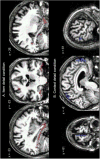

This study investigated the impact of Alzheimer׳s disease (AD) on conjunctive and relational binding in episodic memory. Mild AD patients and controls had to remember item-color associations by imagining color either as a contextual association (relational memory) or as a feature of the item to be encoded (conjunctive memory). Patients׳ performance in each condition was correlated with cerebral metabolism measured by FDG-PET. The results showed that AD patients had an impaired capacity to remember item-color associations, with deficits in both relational and conjunctive memory. However, performance in the two kinds of associative memory varied independently across patients. Partial Least Square analyses revealed that poor conjunctive memory was related to hypometabolism in an anterior temporal-posterior fusiform brain network, whereas relational memory correlated with metabolism in regions of the default mode network. These findings support the hypothesis of distinct neural systems specialized in different types of associative memory and point to heterogeneous profiles of memory alteration in Alzheimer׳s disease as a function of damage to the respective neural networks.